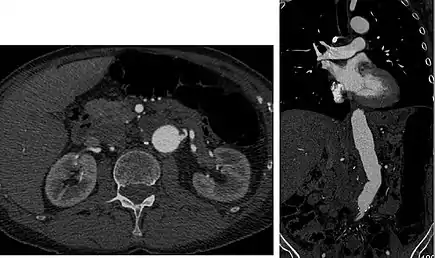

Aorta and great arteries

CTA can be used in the chest and abdomen to identify aneurysms in the aorta or other major blood vessels. These areas of weakened blood vessel walls that bulge out can life-threatening if they rupture. CTA is the test of choice when assessing aneurysm before and after endovascular stenting due to the ability to detect calcium within the wall.[2] Another positive of CTA in abdominal aortic aneurysm assessment is that it allows for better estimation of blood vessel dilation and can better detect blood clots compared to standard angiography.[3]